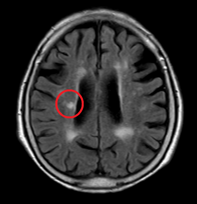

脳ドックMRI検査のご案内

脳ドックとは

脳血管疾患(脳卒中)の死亡率は、厚生労働省のデータ(令和6年、2024年)では、全死因の6.9%を占め、死因の第4位です。 脳ドックとは、脳疾患の早期発見に役立ち、健康を守る重要な手段です。特に脳卒中や認知症のリスクを早期に特定し、予防策を講じることができます。また、脳の健康状態を定期的にチェックすることで、生活習慣の改善や適切な医療ケアを受けるきっかけにもなります。 |

何がわかるのか

・無症候性脳梗塞(ラクナ梗塞)

症状がなくても脳の血管が詰まることがあり、将来の脳卒中や認知症のリスクを高めます。

・脳微小出血

微細な脳出血のことで、脳卒中のリスクを高めることがあります。

実際の異常所見

![]() 無症候脳梗塞 |

![]() 微小脳出血 |

![]() 脳動脈瘤 |

無症状でもこのような所見がみられることがあります。このように早期で発見し適切な対策を行うことで、病気の進行を遅らせたり、予防することが可能になります。